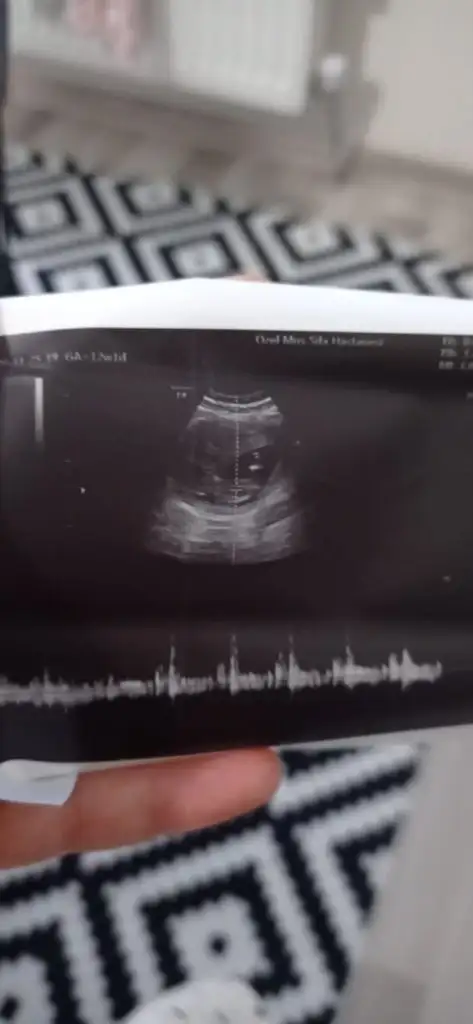

Aminnnnn. Benim de küçük bir adamım var. İnsallah bir de kızım olur. Hamileyim şuan :)

• 20201208_210713_resized.webp

20201208_210713_resized.webp

11,7 KB · Görüntüleme: 58

• 20201208_211103.webp

20201208_211103.webp

14,2 KB · Görüntüleme: 48

• 20201208_211046.webp

20201208_211046.webp

14,1 KB · Görüntüleme: 54